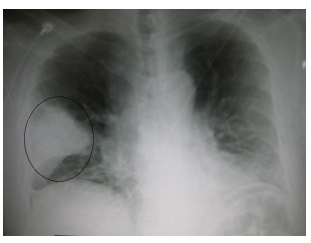

AFC, sexo feminino, 50 anos, portadora de diabetes mellitus não insulino dependente e etilista social, procura atendimento médico se queixando que há 4 dias

iniciou quadro de tosse produtiva, febre de 39,0°C, prostração e dispneia aos médios esforços. Em seu exame físico completo, você verifica crepitações finas em

hemitórax esquerdo e uma taquipneia de 28 IRPM, sem outras alterações relevantes no exame físico. Você solicita uma radiografia de tórax.

Diante do quadro e considerando as principais evidências atuais, entre as alternativas abaixo, qual a MELHOR conduta terapêutica?